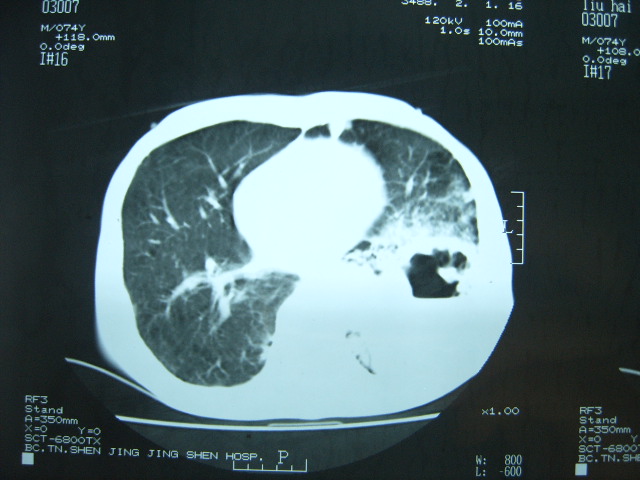

男74岁,咳嗽,寒战,低烧。有糖尿病史。

两肺结核,空洞形成,左下肺肺段隔离症待排

两肺结核,左下肺大片实变,内见空洞性病变,壁不规则,结合糖尿病史,考虑:结核性?霉菌性?建议结合实验室检查或治疗后复查。